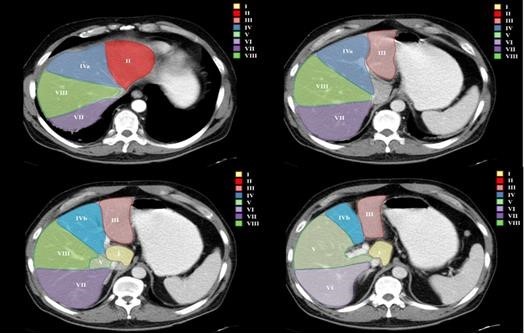

2. El papel de la tomografía computada

La TCMC ha presentado un gran avance en la evaluación diagnóstica de las enfermedades renales por medio de la rápida adquisición de imágenes y del uso de sus diferentes fases, obtenidas de forma secundaria a la administración del medio de contraste endovenoso. Describiremos cada fase y su importancia 3-4.

Fase corticomedular y arterial

Esta primera fase ocurre en los primeros 25 a 70 segundos posteriores a la inyección del medio de contraste; la corteza renal, al retener el medio de contraste en este tiempo en los capilares corticales aumenta de una manera intensa diferenciándose de la médula renal, que se encuentra hipodensa.

La fase arterial o corticomedular es esencial para la estadificación, extensión y planificación quirúrgica, si fuese el caso de la neoplasia encontrada, ya que ofrece un mejor detalle vascular (opacificación de los vasos), una mayor definición anatómica y de lesiones vascularizadas en el hígado, el bazo o el páncreas, consideradas dentro del contexto de una metástasis (Fig. 2).